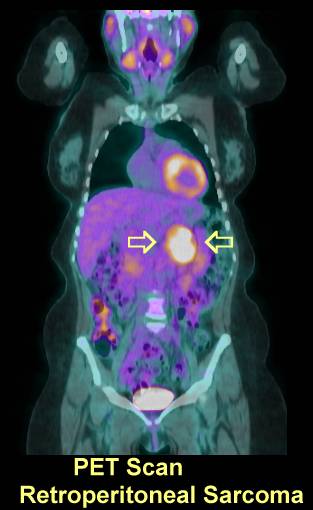

(For a picture of a retroperitoneal sarcoma see CT here and PET scan here, here and here).

PET Scan